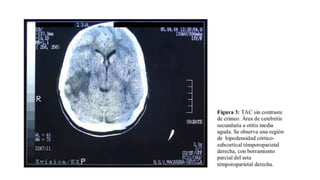

demostrada mediante TAC.

focalidad neurológica, con una rápida evolución. El diagnóstico se lleva a cabo mediante TAC; se